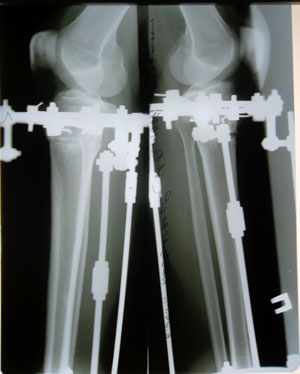

Рентген в 48 дней.

Отлично срастается, скоро на снятие аппаратов! 094f316296.gif